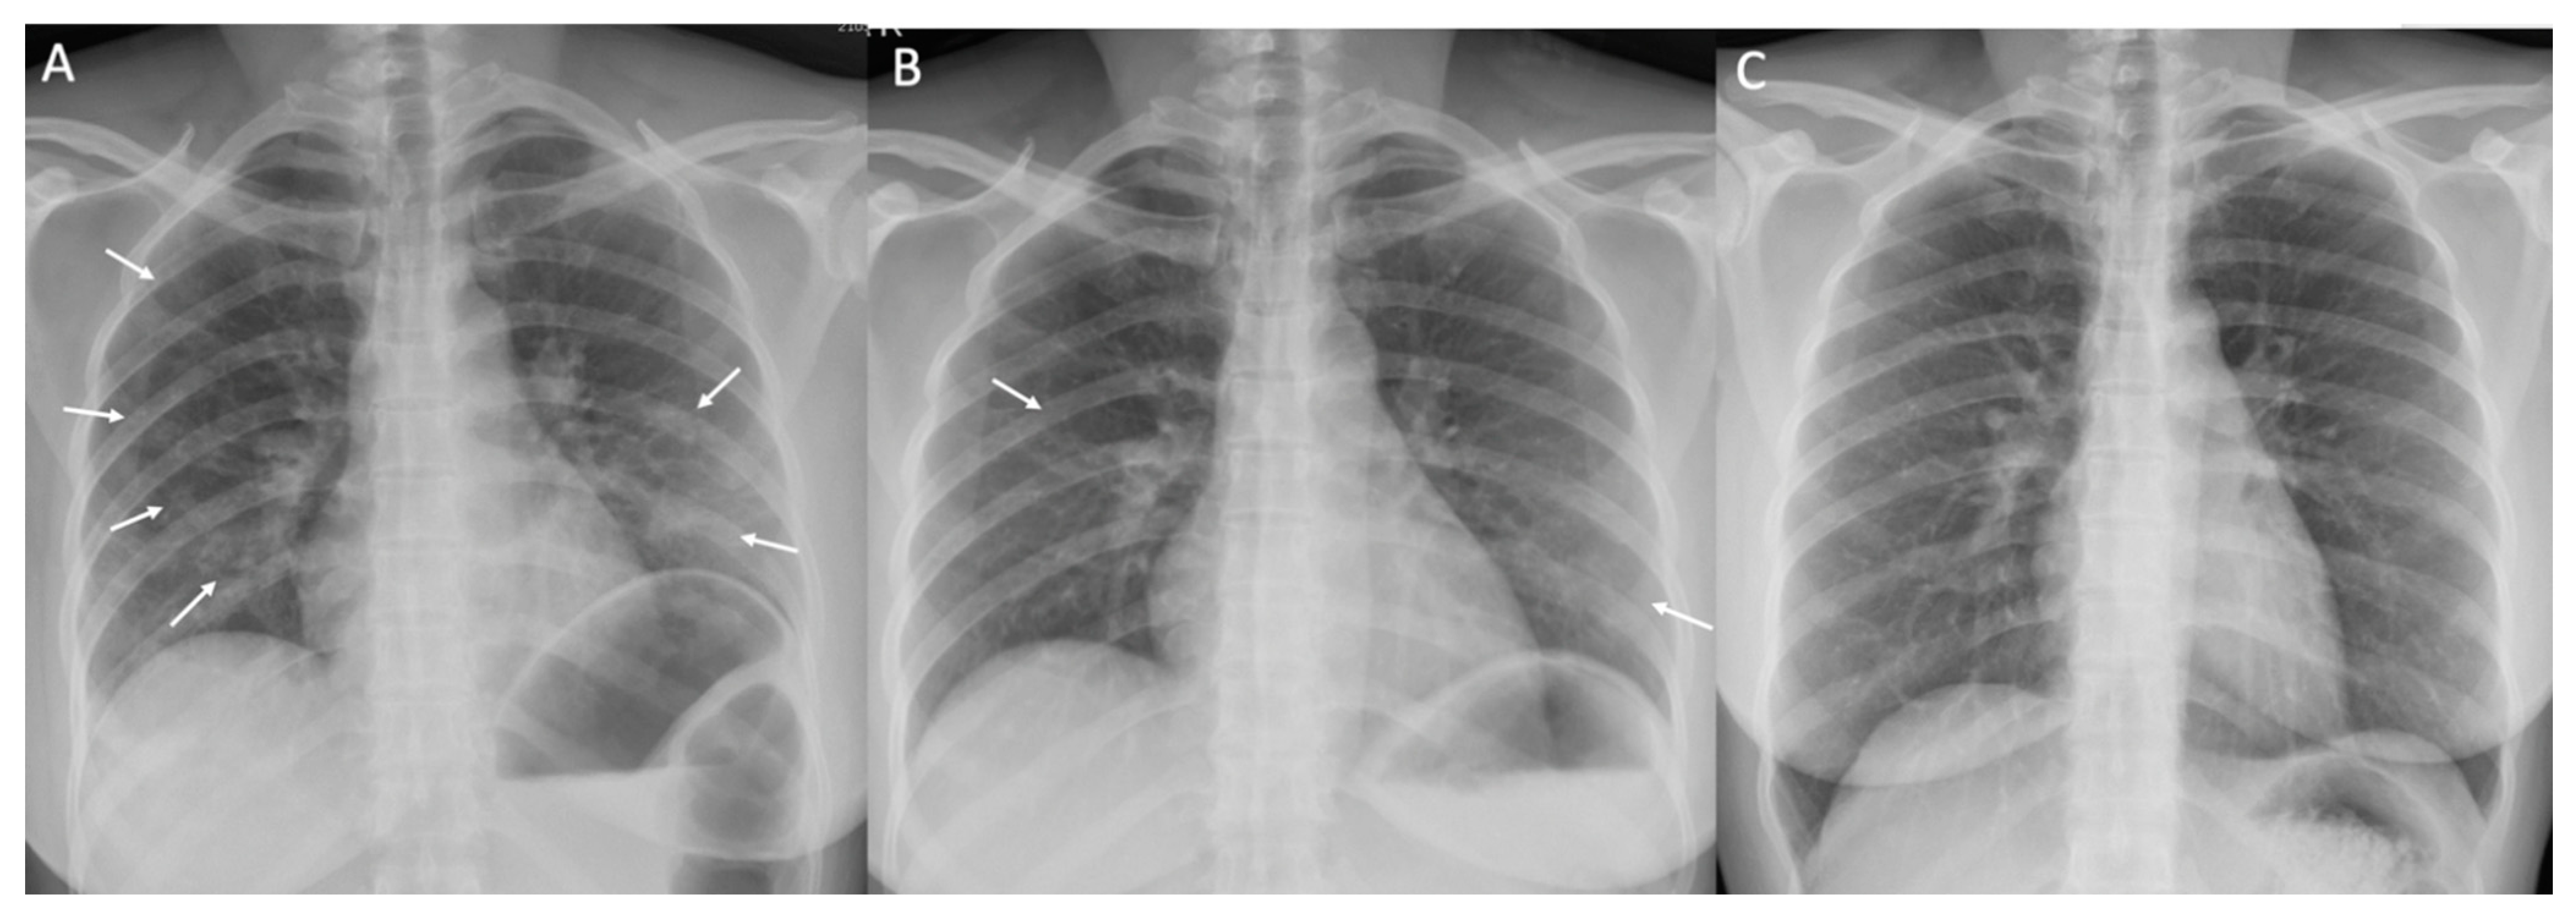

2.3. Radiographic Assessment

| Normal chest X-ray on DOI 1–3, n (%) | 211/290 (72.7) | 47/57 (82.5) | 163/231 (70.6) | 1/2 (50) | 0.136 |